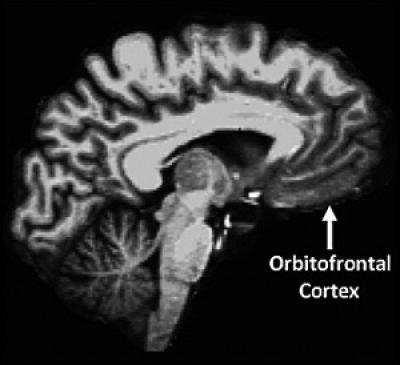

image: The orbitofrontal cortex, which is part of the prefrontal region and involved in social/emotional processing, showed similar associations with personality. view more